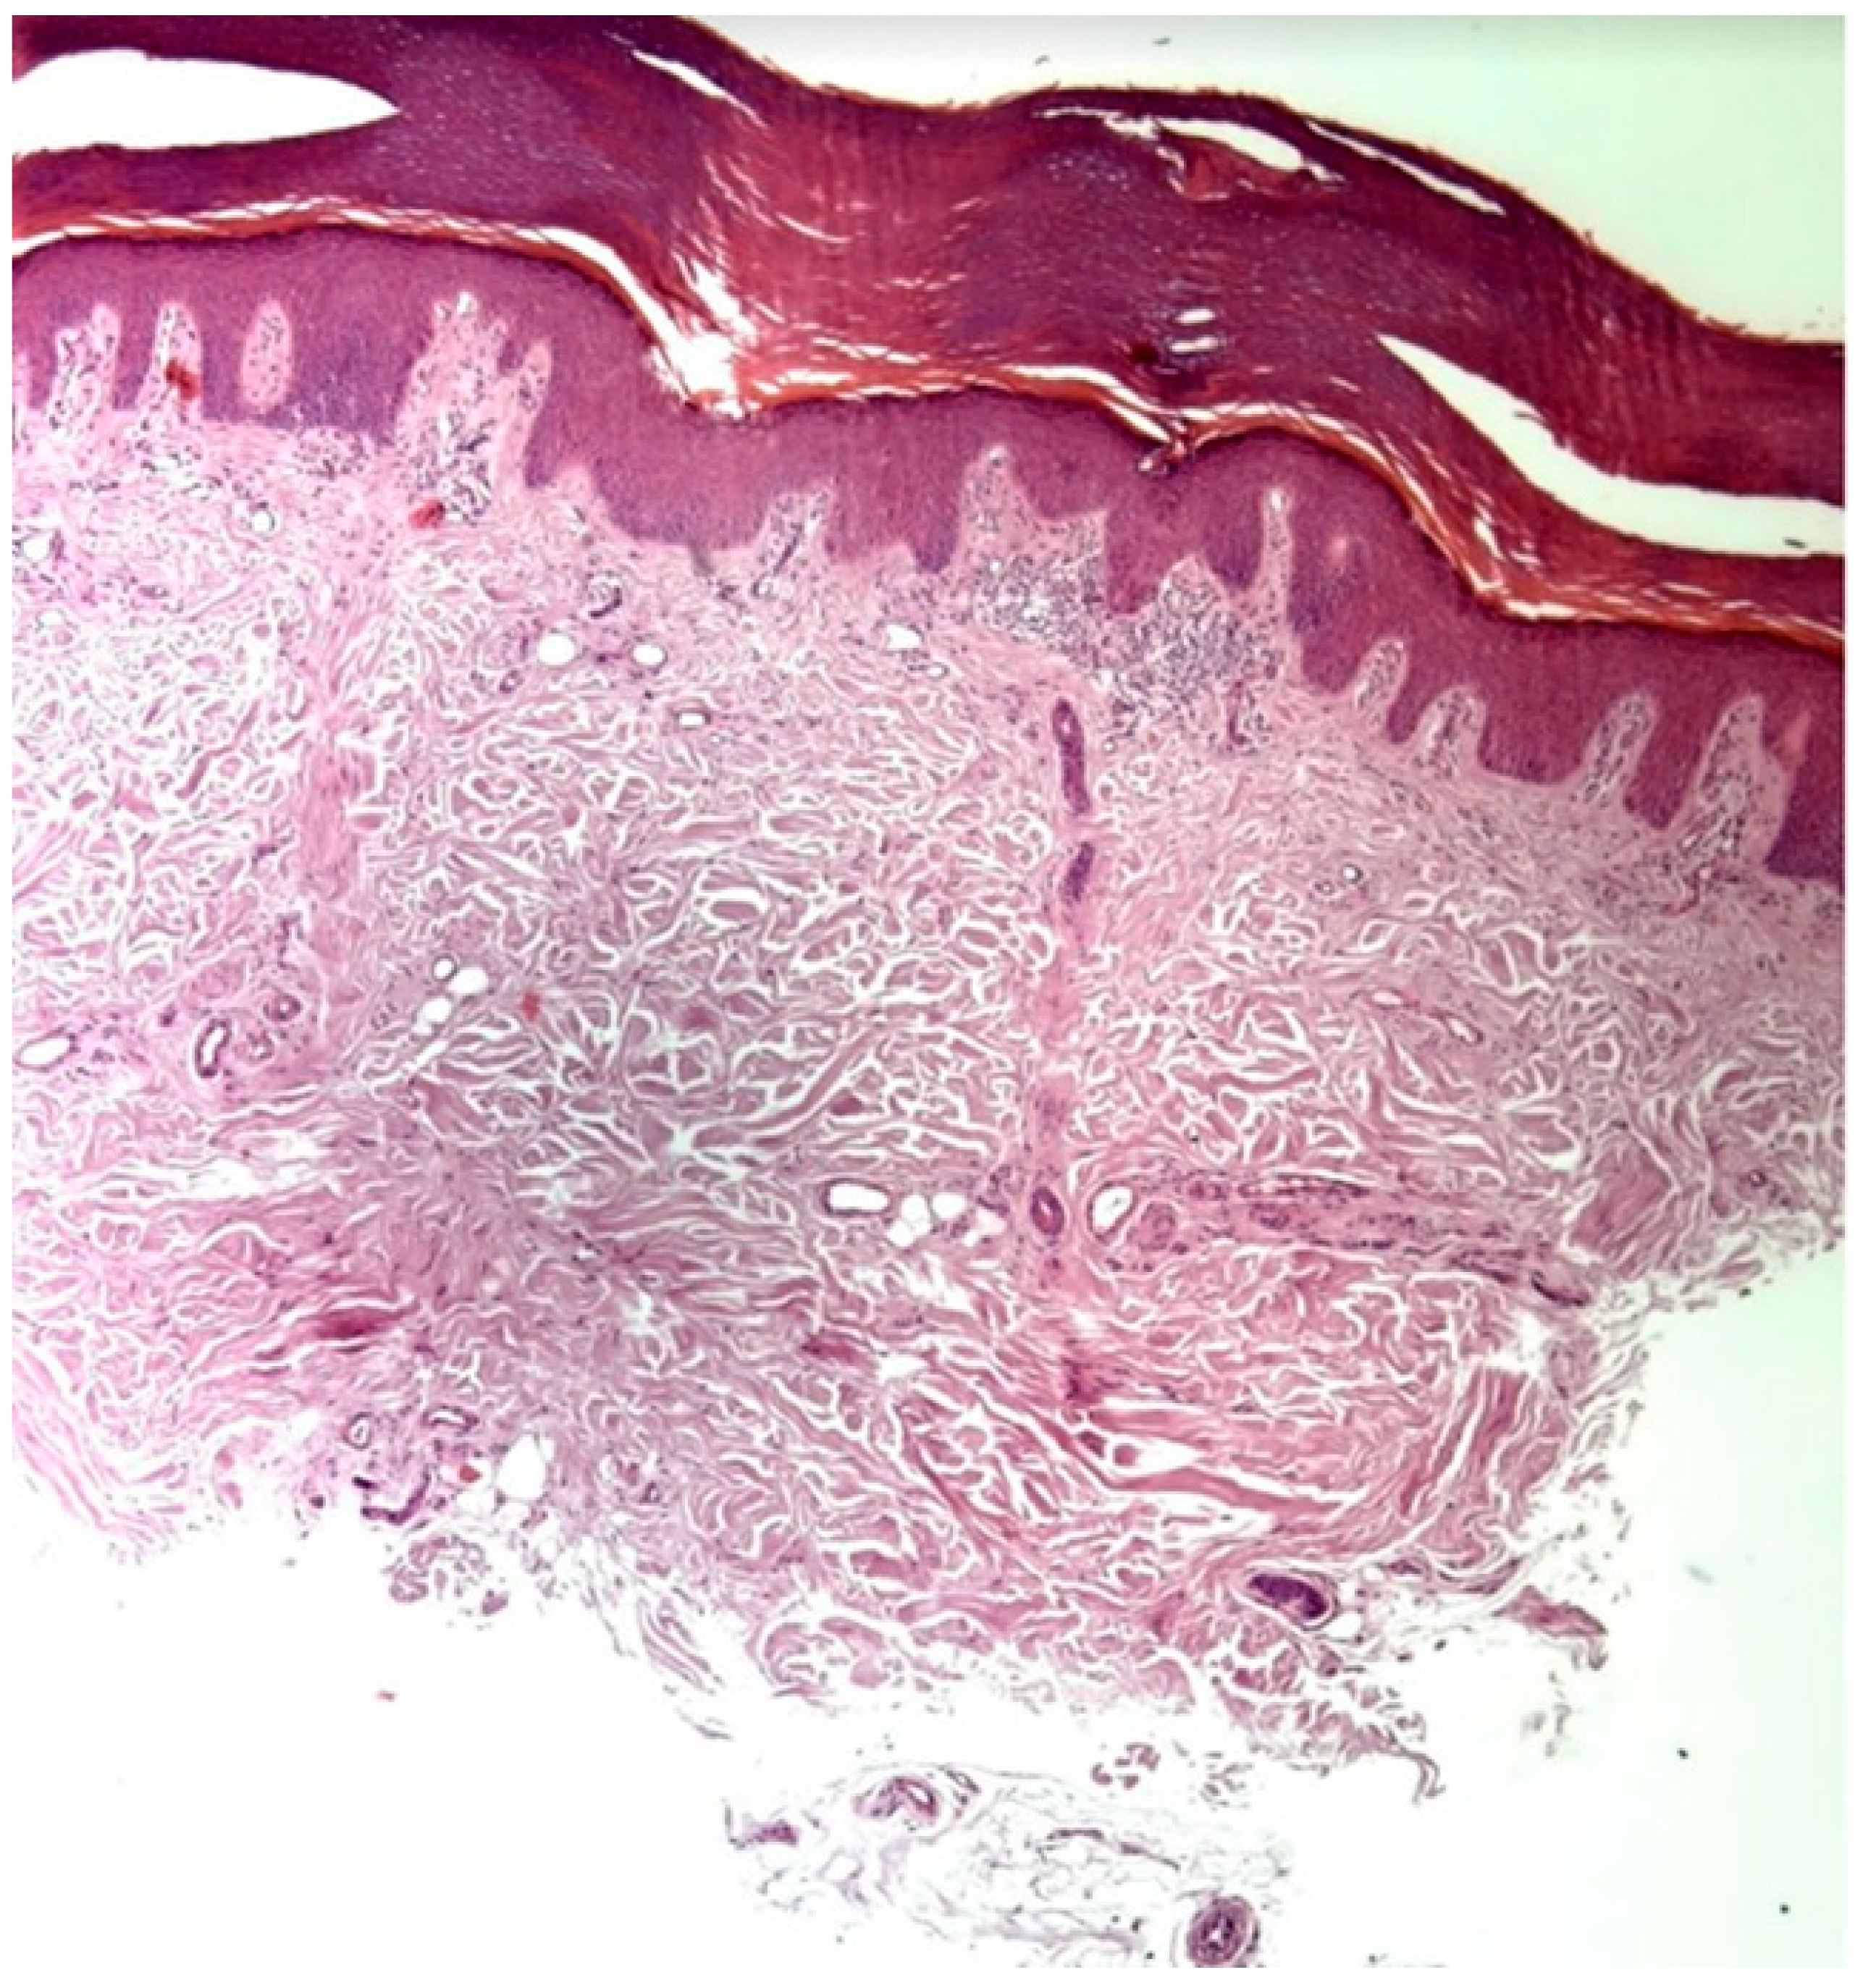

Further skin biopsies from unaffected skin from the right hand and left armpit were conducted to assess the presence and structure of sweat glands. The histology report of the right hand sample revealed a markedly reduced number of eccrine glands, with those present displaying signs of atrophy and ductal fibrosis, attributed to fibrotic bands oriented perpendicular to the epidermis. The number of acrosyringia was also significantly diminished, with the remaining structures showing abnormal keratinization and dyskeratotic cells. This process appears complete. Scattered lymphocytes and mast cells were present around the few remaining eccrine glands, which exhibited signs of atrophy. The microscopic examination thus indicated destruction with subsequent fibrosis of the eccrine glands and their ducts (Figure 4). Similarly, in the sample from the left armpit, a loss of eccrine sweat glands was observed. Additionally, a sample of the fragment of the tattoo from the right forearm was taken, but from the area of the blue pigment, to assess whether there was a hypersensitivity reaction to components of the tattoo other than the red pigment. No histological features indicating a hypersensitivity reaction were described, and additionally, no acrosyringia were found. These findings suggest a very low likelihood of sweat function recovery, although complete irreversibility cannot be stated with absolute certainty. Our treatment focuses on therapy for vitiligo and alopecia.

Figure 4. The histological image of the skin biopsy from the right hand shows destruction and subsequent fibrosis of the eccrine glands and their excretory ducts (40×).